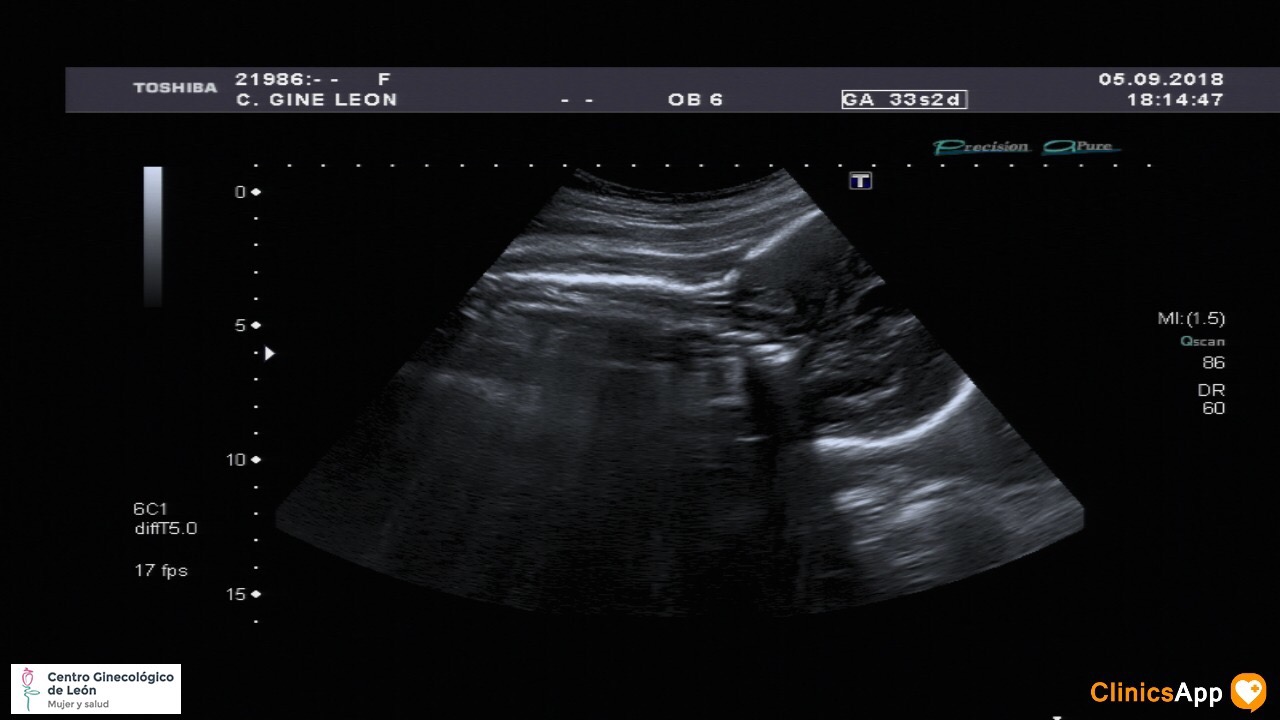

Nueva ecografía de la hermana de Mateo Nueva ecografía… y aún sin nombre. Ya pesa más de 2Kg, así que empieza a estar más apretada. Fecha publicación 05/09/2018 Publicada por papá Publicada en Fotos, Galerías, Prenatal Comentarios 0 Entrada anterior: Con mamá al parque Entrada siguiente: Caco balí n° 23 Deja una respuesta Cancelar la respuestaComentario * Nombre * Correo electrónico * Web Guarda mi nombre, correo electrónico y web en este navegador para la próxima vez que comente. Recibir un correo electrónico con los siguientes comentarios a esta entrada. Δ